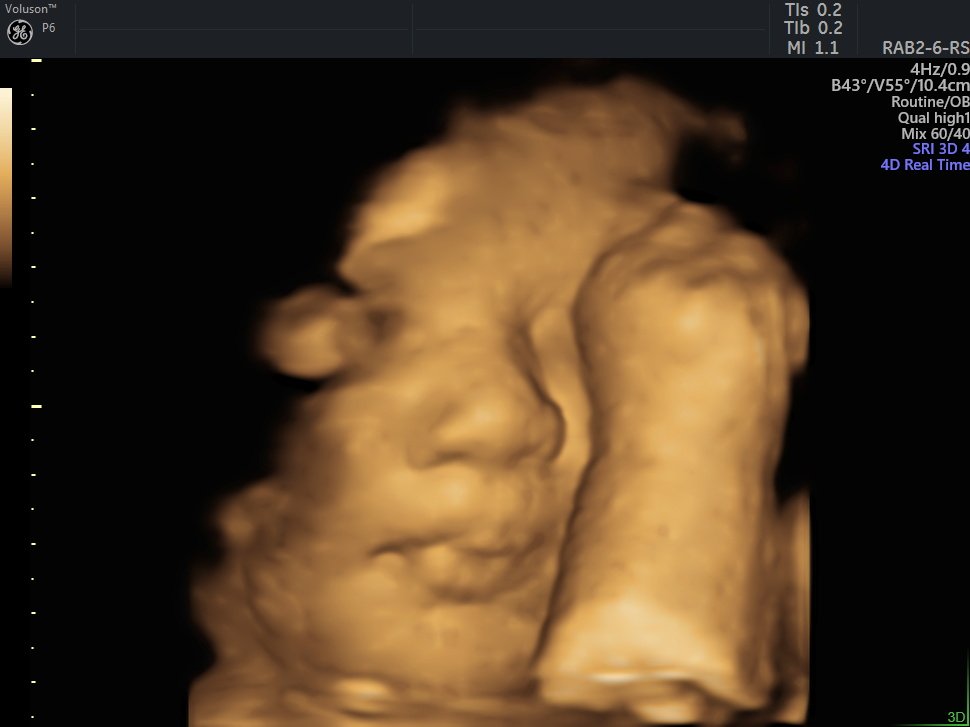

4 Boyutlu (Renkli) Ultrason ve Doppler Ultrasonografi

4 D Ultrasonografi